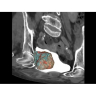

Травматология и ортопедия

• Диагностика сложных переломов и повреждений суставов.

• 3D-реконструкция костных структур для планирования операций.